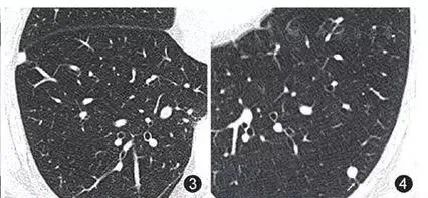

吸入有机粉尘同样也可引发肺结节的形成,例如采棉工人的棉尘肺、吸入谷物粉尘的农民肺以及暴露于木尘的木工等。下图是一位采棉女工,长期吸入植物性粉尘,在肺里形成很多微结节和索条状影。